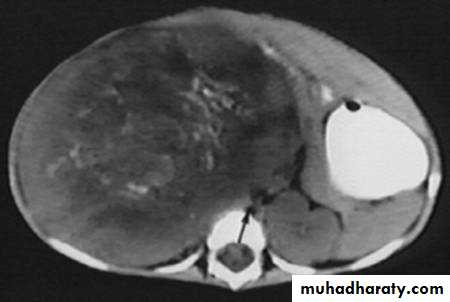

RENAL TUMOR Adenocarcinoma ( Hyper nephroma)

* Comprise 80% of renal malignant tumor. next epithelial T. of renal pelvis (transitional cell Ca.) ; Nephroblastoma ( Wilm’s Tumor ).* Clinically may be silent or presented with loin pain , heamaturia and loin mass .

IVU :-

* Nephrogram shows filling defect which is irregular .* Distracted PCS .

* Hydronephrosis.

* Amputation & missing calyces .

* Large non-functioning kidney .

CT

MRI